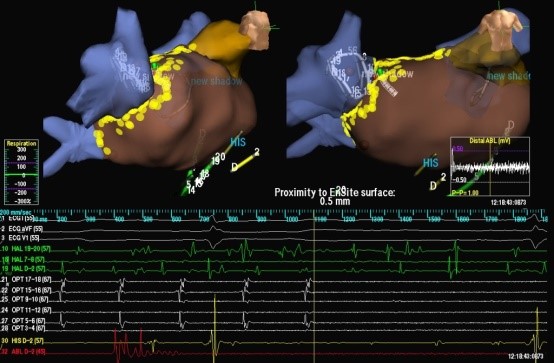

Ablación por radiofrecuencia punto por punto. Utiliza un sistema de mapeo no radioscópico, cuyo software permite reconstruir una cascara interna de la cavidad cardíaca (AI y venas pulmonares) sobre la cual una vez definida (primera etapa: Reconstrucción geométrica) se procede a realiza lesiones con un catéter de ablación (segunda etapa: Ablación) alrededor de las venas pulmonares, en su desembocadura a la AI hasta lograr el aislamiento eléctrico de las mismas, es decir desconectar eléctricamente las venas pulmonares de la AI.

Figura II: a la izquierda esquema de ablación punto por punto alrededor de las venas pulmonares. A la derecha sistema de mapeo no radioscópico con lesiones en amarillo alrededor de las Venas pulmonares derechas observándose en el registro endocavitario en blanco el aislamiento.